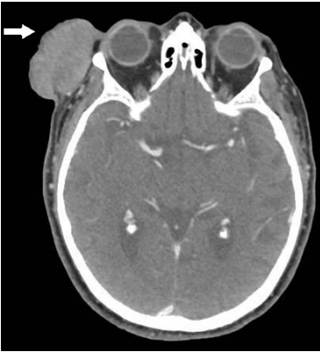

Previamente, a la paciente se le había realizado una biopsia de la lesión tumoral cutánea por parte del servicio de Dermatología, con diagnóstico anatomopatológico de carcinoma neuroendocrino. Como exámenes complementarios se le realizó una tomografía computarizada que mostró una tumoración exofítica en la piel de la sien derecha, sin compromiso del músculo temporal. La lesión llegaba a contactar con el párpado superior, sin demostrarse afectación de la glándula lacrimal (Figura 2). Se encontró además un ganglio de seis mm en el lóbulo superficial de la parótida derecha, un nódulo necrosado de siete mm en el espacio carotídeo derecho, así como ganglios cervicales laterales derechos de hasta 13 mm, de aspecto patológico.